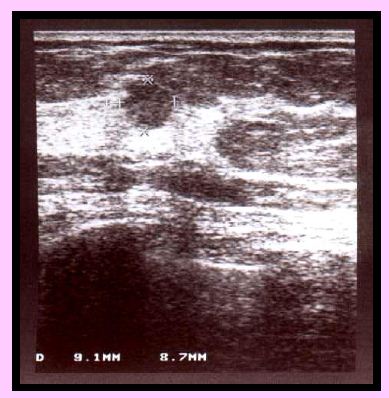

Nehmatné

RA: 0

HRT: 0